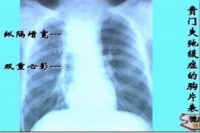

1.钡餐检查 钡餐常难以通过贲门部而潴留于食管下端,并显示为1~3cm长的、

贲门失弛缓症

对称的、粘膜纹政党的漏斗形狭窄,其上段食管呈现不同程度的扩张、处长与弯曲,无蠕动波。如予热饮,舌下含服硝酸甘油片或吸入亚硝酸异戊酯,每见食管贲门弛缓;如予冷饮,则使贲门更难以松弛。潴留的食物残渣可在钡餐造影时呈现充盈缺损,故检查前应作食管引流与灌洗。

2.胸部平片 本病初期,胸片可无异常。随着食管扩张,可在后前位胸片见到纵隔右上边缘膨出。在食管高度扩张、伸延与弯曲时,可见纵隔增宽而超过心脏右缘,有时可被误诊为纵隔肿瘤。当食管内潴留大量食物和气体时,食管内可见液平。大部分病例可见胃泡消失。